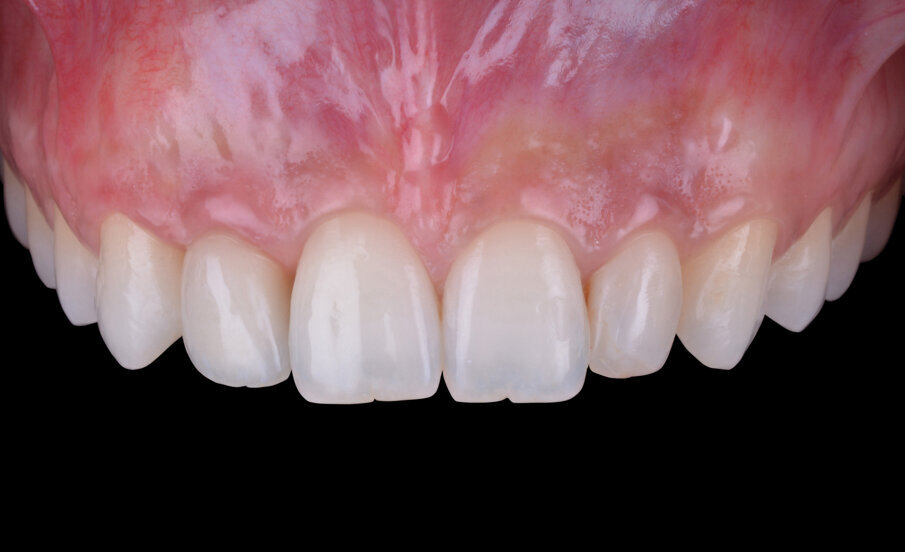

L’elemento dentario 1.2 riabilitato per mezzo di una corona avvitata su impianto dimostra una corretta e piacevole integrazione estetico-funzionale (Figg. 16, 17). I tessuti molli perimplantari sono caratterizzati da un corretto trofismo cervicale e un buon mimetismo radicolare; il fenotipo gengivale spesso ha agevolato il raggiungimento di un gradevole equilibrio estetico tra corona e tessuti molli e garantisce un sigillo transmucoso in grado di proteggere l’interfaccia abutmentimpianto e assicurare la stabilità della riabilitazione nel lungo periodo.

Fig. 2 - Situazione clinica iniziale (visione frontale).